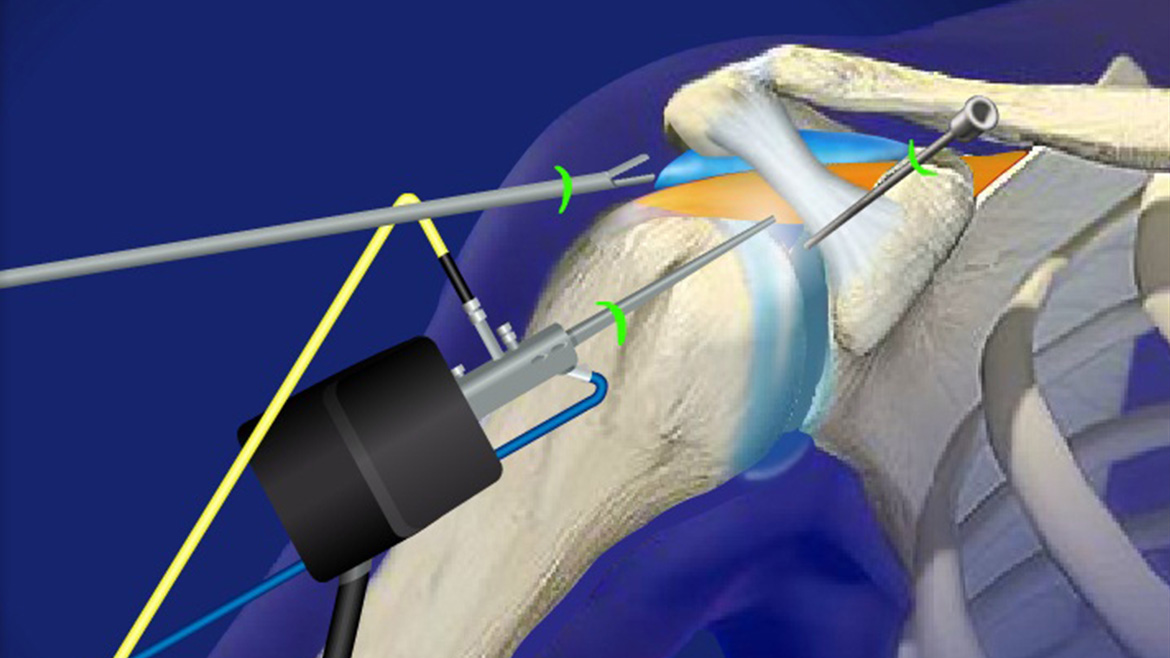

Супрапателлярный импиджмент коленного сустава: симптомы и лечение